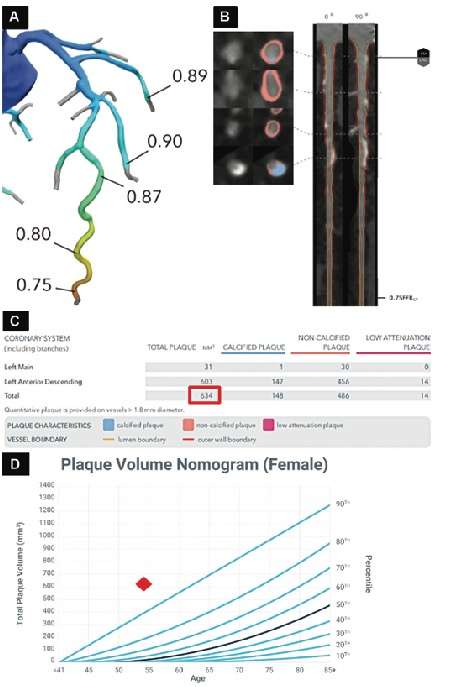

下图为一名 54 岁自述呼吸困难的女性患者的基于人工智能软件的斑块总量和斑块分类结果

A :显示 CT 分数血流储备值正常,表明没有结构性冠状动脉斑块;颜色编码表示血流阻塞的严重程度,数值小于 0.8 表示生理血流阻塞。

B:心脏 CT 斑块量化软件图像显示斑块亚型的识别、量化和颜色编码;例如,橙色表示非钙化斑块,蓝色表示钙化斑块。

C:图表显示每血管斑块亚型分析,斑块亚型和斑块总体积(红框)为 634 立方毫米。

D:Nomogram图显示患者的斑块体积处于第 99 百分位数(红色菱形)。Nomogram图来自于Ref 17,基于 10,000 多例心脏 CT 扫描。